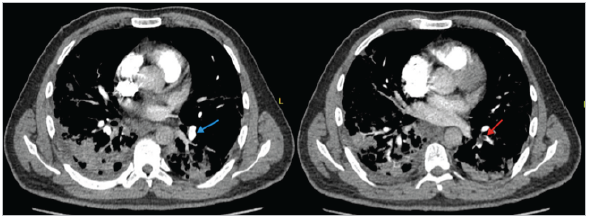

Hombre de 50 años con antecedente de hipertensión arterial quien ingresa a urgencias con cuadro de dos horas de evolución de hemiparesia derecha y disartria con NIHSS de ingreso de ocho, signos vitales: tensión arterial 190/100 mmHg, frecuencia cardiaca 80 lpm, frecuencia respiratoria 23 rpm, SaO2 83% y glucometría en 382 mg/ dL; es llevado a RMN cerebral simple con evidencia de restricción en la difusión del tálamo derecho y frontal izquierdo no evidente en Flair (Figura 1). Se inicia manejo con la labetalol logrando control de presión arterial, se procede a trombolisis con rTPA/alteplasa, a las 24 horas con NIHSS de 1. La radiografía de tórax de ingreso evidencia infiltrados difusos en ambos campos pulmonares compatibles con infección por COVID-19. RT PCR para SARS-CoV-2 inicial negativa, por lo que ante alta sospecha clínica al día siguiente se realiza prueba confirmatoria con resultado positivo. Se realiza diagnóstico de diabetes mellitus por HbA1C 10%. En la pesquisa neurovascular se realiza Doppler de vasos de cuello, electrocardiograma y ecocardiograma los cuales se encontraban dentro de límites normales. Luego de cinco días de hospitalización presenta dolor torácico de característica pleuríticas asociado a diaforesis y desaturación por lo cual se toma electrocardiograma con evidencia de taquicardia sinusal, troponina negativa y angioTAC evidenciando tromboembolismo pulmonar agudo bilateral a nivel del lóbulo inferior izquierdo y lóbulo superior derecho (Figura 2). Luego de 18 días de hospitalización se da egreso con única secuela neurológica mono hipoestesia de miembro superior derecho con oxígeno por cánula nasal a dos litros.

Figura 1 Caso 1. Resonancia magnética cerebral simple en ventana DWI (A, B y C) y T2 FLAIR (D y E) se evidencian áreas de infarto hiperagudo en lóbulo frontal izquierdo y lacunar talámico derecho.